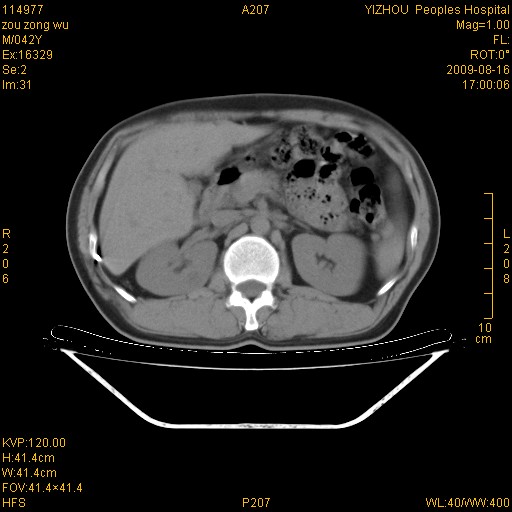

以下是引用zjzjr在2009-8-17 10:42:00的发言:[br]右侧间质性肺炎伴纤维化,右肺下叶肺囊肿伴感染(不除外外伤后引起),右肺野及胸壁软组织\\肝内见多发斑点状,中枪了吧.右侧胸膜肥厚\\粘连.